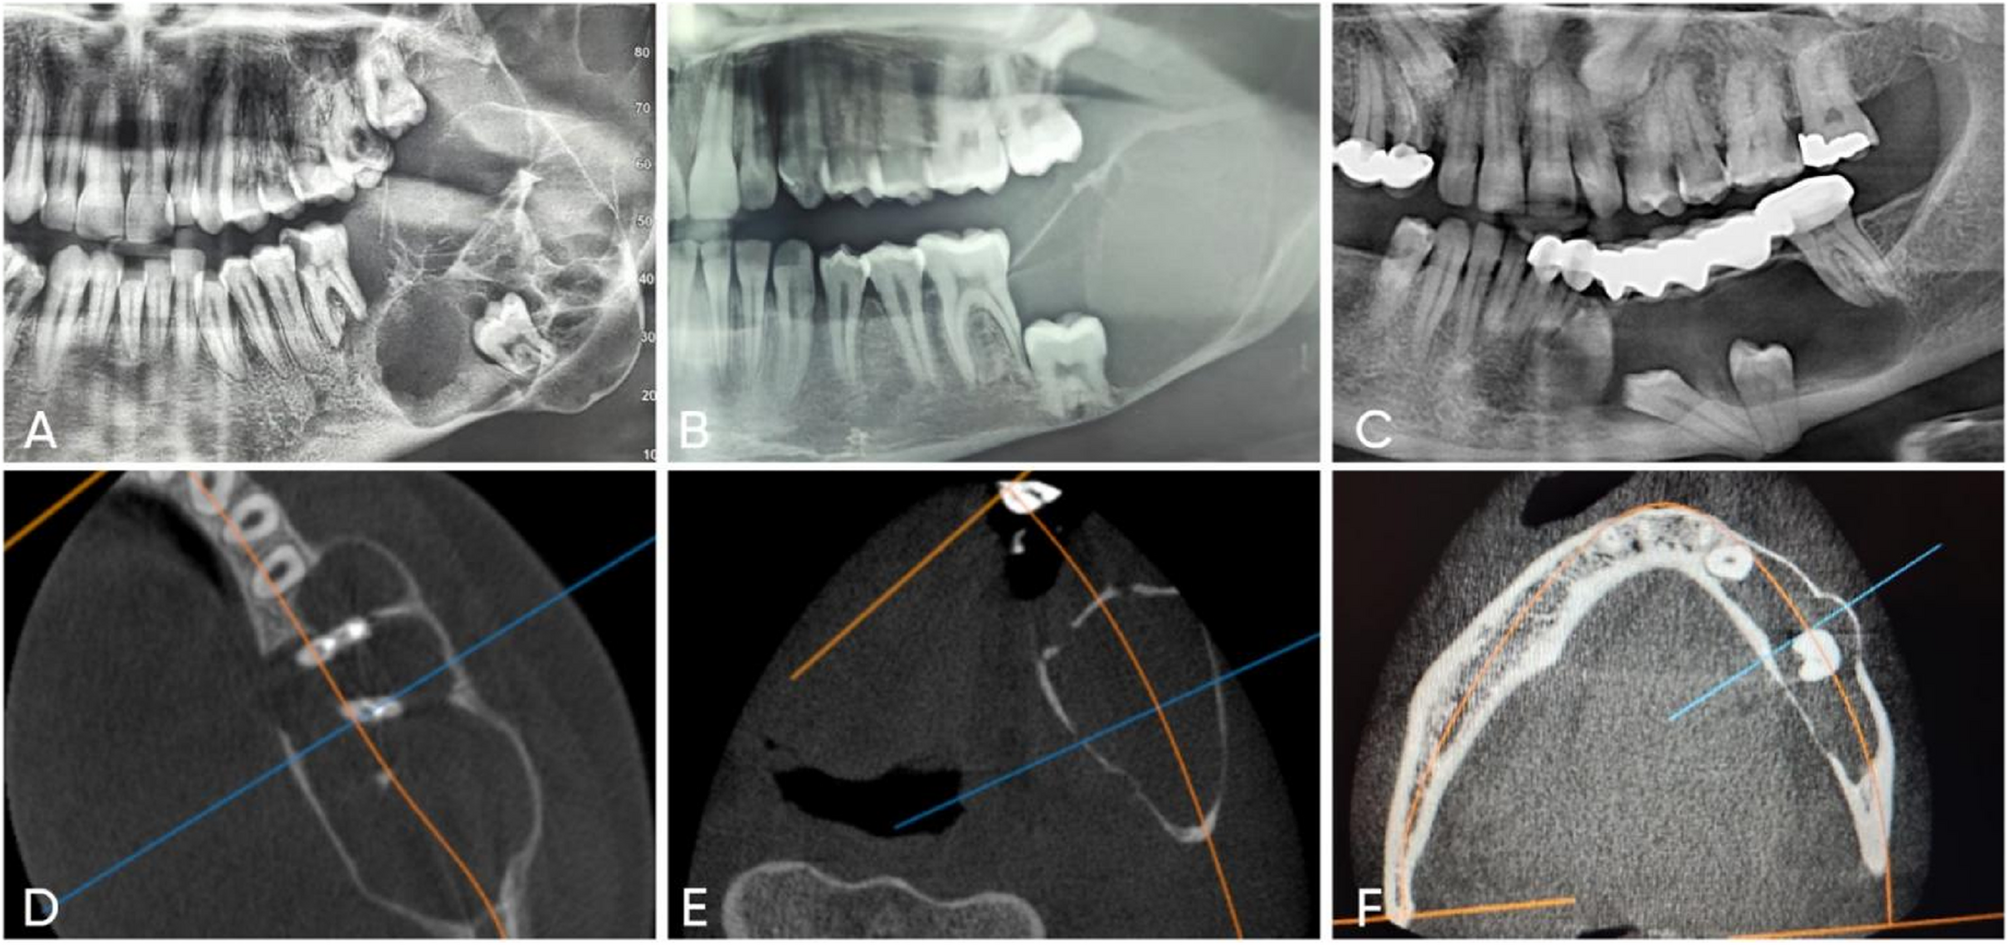

Evaluation of the prognostic role of SOX2 as a tumor stem cell marker in odontogenic cysts and tumors: clinical, radiographic and immunohistochemical correlation | BMC Oral Health